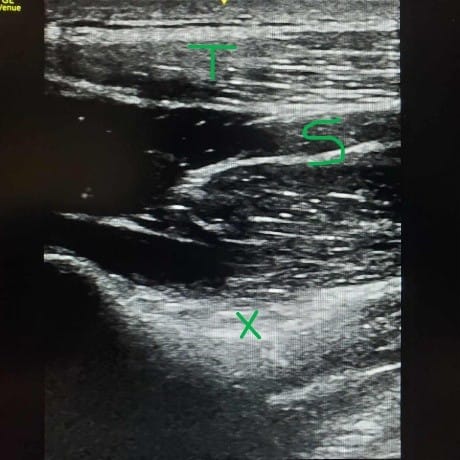

Now on to the selective axillary nerve block. Keep patients in the same sitting position, but now have them let go of the contralateral shoulder and relax their arm by their side. Place the probe in the sagittal position on the posterolateral side of the humeral head. After locating the head of the humerus, scan caudad to the transition between the humeral metaphysis and diaphysis. As the straight line of diaphysis now curves into the metaphysis, put the color setting on the ultrasound machine and identify the posterior circumflex humeral artery and the small axillary nerve running in the fascial compartment between teres minor and the deltoid muscles.11 Just like in the approach to the suprascapular nerve, a nerve stimulator can help to identify an axillary nerve that is difficult to visualize on ultrasound. Look for a deltoid and/or teres minor twitch if using a nerve stimulator. Place 10 ml of local anesthetic into or deep to the fascial compartment containing the axillary nerve and the posterior circumflex humeral artery. The nerve is not always visible, so identifying the bony, muscle, fascial, and arterial landmarks is important. Injecting into or deep into the fascial compartment containing the nerve is sufficient to block this nerve. The injection doesn’t need to be immediately adjacent to the nerve. If the nerve isn’t visualized, it’s advisable to inject deep into the fascial compartment where the shaft of the humerus transitions to the head of the humerus to avoid nerve injury.